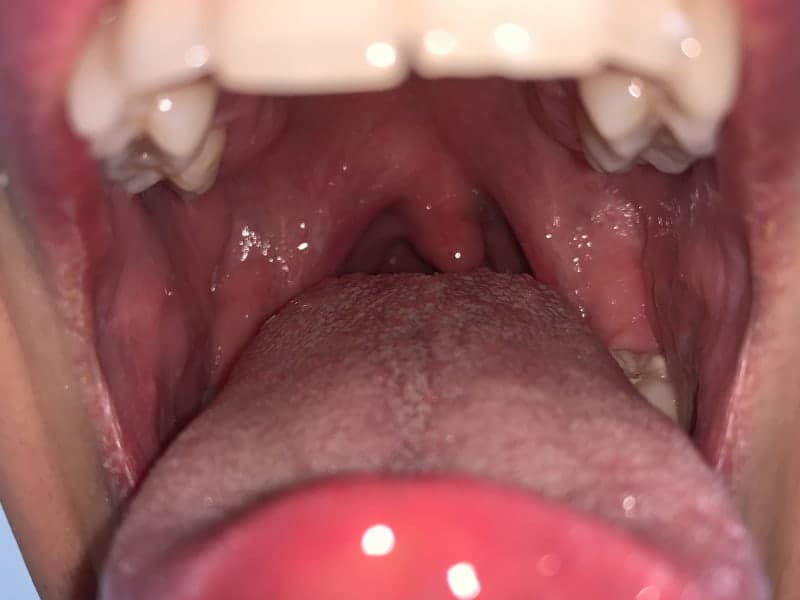

Does Viral Tonsillitis Get Worse Before Better . Viral infections such as colds and flu. if you have tonsillitis from a viral infection, such as the common cold or flu, your symptoms may be milder than if the cause is. But if tonsillitis is caused by strep throat,. viral tonsillitis typically goes away on its own in about one week. Bacterial infections such as group a. generally, viral tonsillitis is less severe and more common than bacterial tonsillitis, making up about 70% of cases. tonsillitis can be caused by: Bacterial tonsillitis takes about 10 days to run its. if tonsillitis is caused by a viral infection, you may be able to manage symptoms at home without medication. strep throat can make your throat and tonsils red, sore, swollen, and filled with white patches or pus, making. viruses are the most common cause of tonsillitis in adults and children, being responsible for up to 70% of cases, according to the.